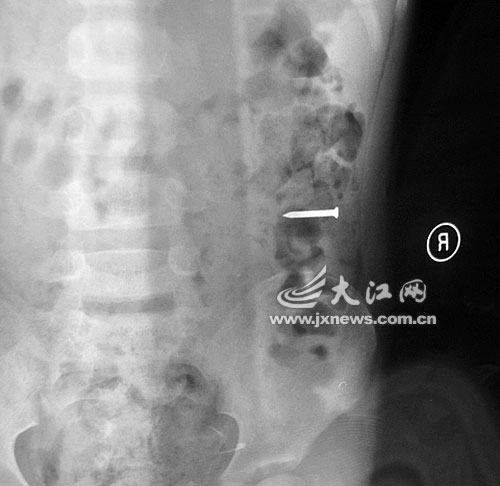

事發(fā)當(dāng)晚,勇勇的奶奶雇了一輛面包車(chē),連夜將勇勇送往都昌縣人民醫(yī)院救治。當(dāng)晚,醫(yī)院經(jīng)過(guò)拍片發(fā)現(xiàn),2.5厘米的鐵釘滑到孩子的胃部。

當(dāng)晚7時(shí)20分許,勇勇突然將這枚長(zhǎng)達(dá)2.5厘米的鐵釘吞進(jìn)肚子,并疼得渾身冒汗。